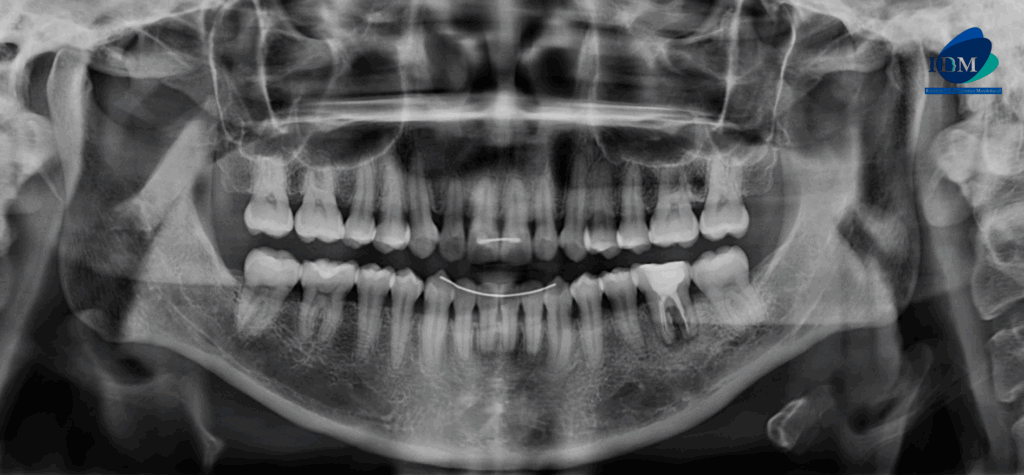

Radiografia Panorámica

A la evaluación de la radiografía panorámica se observa aplanamiento de contornos condilares, neumatización de ambos senos maxilares, presencia de dispositivos de ferulización anterosuperior y anteroinferior, ausencia de terceras molares y múltiples restauraciones, también observamos la pieza 36 con material restaurador coronario, sellado cameral y obturación de conductos con un proceso osteolítico interradicular y una imagen radiolucida en raíz distal.